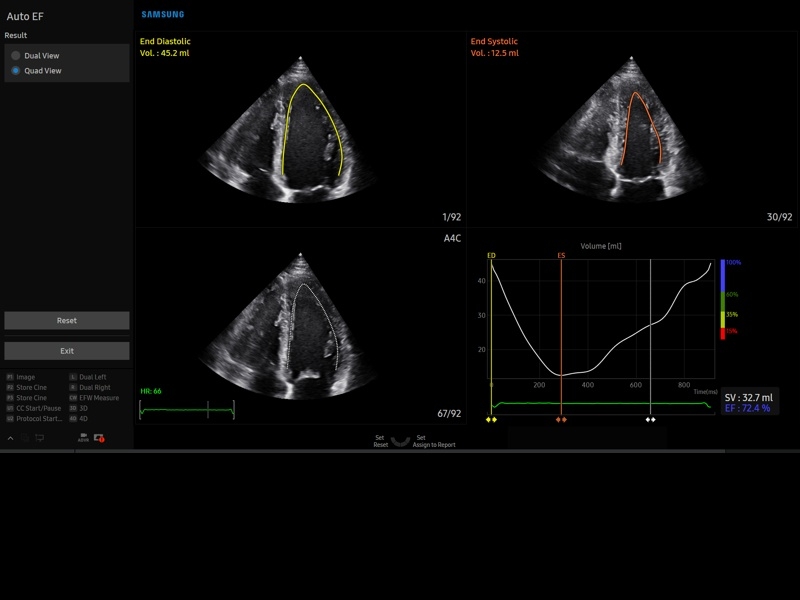

• Кардиологический пакет с функцией StressEcho

• Кардиопакет: тканевый допплер (TDI) + анатомический М-режим + цветной М-режим (CM) + программное обеспечение.

• МодульStrain+- программа не векторной оценки степени сократимости миокарда с выведением автоматически расчетов и графиков на экране отдельно по каждому сегменту.

• Модуль Stress Echo – программа для исследования сердца под нагрузкой.

• Пакет кардиологических исследований.

М-режим:измерение диаметра аорты, передне-заднего размера ЛП, толщины МЖП (систолическая и диастолическая), толщины ЗСЛЖ (систолическая и диастолическая), размеров ЛЖ и ПЖ (систолический и диастолический), ФВ (Teichholz).

B-режим:измерение диаметра аорты (восходящей, дуги, нисходящей, на уровне синусов Вальсальвы, на уровне створок аортального клапана), определение размеров ЛП и ПП (максимальный, минимальный, систолический, диастолический, переднее-задний, верхнее-нижний, медиально-латеральный), расчет объемов ЛП и ПП, объемов ЛЖ (метод "Площадь-Длина", метод дисков (Simpson)), массы миокарда ЛЖ, индекса массы миокарда ЛЖ.

CD-режим (ЦДК):измерение радиуса ПФСМР (PISA), полуколичественная оценка трансмитрального, транстрикуспидального, трансаортального и транспульмонального кровотока (оценка регургитации), оценка аномальных сбросов крови через МПП И МЖП.

PW-режим (импульсно-волновой допплер):автоматическая, полуавтоматическая и ручная трассировка допплеровского спектра митрального, аортального и трикуспидального клапанов, клапана легочной артерии, кровотока в выходном тракте ЛЖ и ПЖ (пиковая/средняя скорость, пиковый/средний градиент давления, время изоволюметрического расслабления ЛЖ, время ускорения, замедления, выброса), оценка кровотока легочных и печеночных вен.

CW-режим (постоянно-волновой допплер):программы расчета работы митрального, аортального и трикуспидального клапанов, клапана легочной артерии.

TD-режим (тканевой допплер):количественная оценка локальной сократительной функции стенок ЛЖ и ПЖ.

Сокращения:ЛП/ПП - левое/правое предсердие, МЖП - межжелудочковая перегородка, МПП - межпредсердная перегородка, ЗСЛЖ - задняя стенка левого желудочка, ЛЖ/ПЖ - левый/правый желудочек, ФВ - фракция выброса, ПФСМР - площадь формирующейся струи митральной регуритации (PISA - proximal isovelocity surface area), ПСС/КДС - пиковая систолическая / конечная диастолическая скорость.